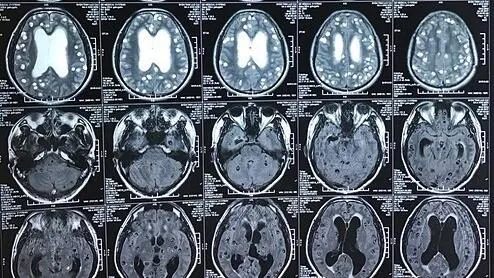

Hội chứng hai bé gặp phải còn gọi là hội chứng HHE, là một bệnh hiếm gặp được phát hiện lần đầu vào năm 1960. Bệnh có trạng thái co giật nửa người kéo dài trên trẻ sốt dưới 4 tuổi, gây liệt nửa người cùng bên co giật và teo não bán cầu đối bên.

Bác sĩ Việt nhấn mạnh, ở giai đoạn cấp tính, bệnh nhân xuất hiện nhiều cơn co giật khó kiểm soát, tổn thương và phù não một bên bán cầu não. Nếu không kiểm soát tốt, bệnh nhân có thể liệt nửa người suốt đời, di chứng não và sống đời sống thực vật, thậm chí có thể tụt não dẫn đến tử vong.